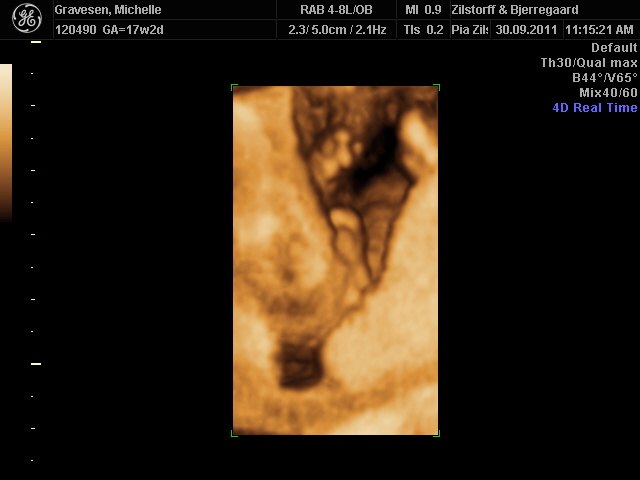

Så fik vi langt om længe klar besked på hvilket køn min kæreste har i maven

Og som flertallet af jer der deltog i billedafstemningen sagde var det det en dreng.

Så vi glæder os begge rigtig meget til at få vores lille supermand til verden